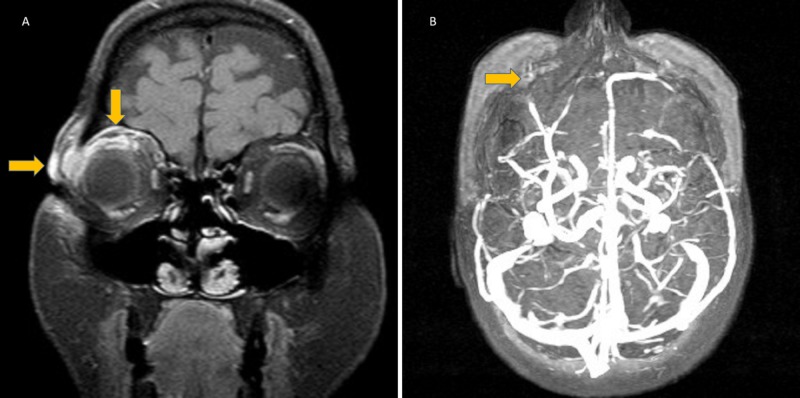

Figure 5. Stingray tail ocular injury. A) T1 SPIR contrast enhancement on a coronal MRI slice displaying right eye subcutaneous edema and periorbital cellulitis. (B) Thrombosis of right eye superior ophthalmic vein.[1]

| current | 18:25, December 23, 2025 | 800 × 398 (69 KB) | Talhah.Zubair (talk | contribs) | Figure 5. Stingray tail ocular injury. A) T1 SPIR contrast enhancement on a coronal MRI slice displaying right eye subcutaneous edema and periorbital cellulitis. (B) Thrombosis of right eye superior ophthalmic vein.38 Copyright © 2020, Ozunal et al. This is an open access article distributed under the terms of the Creative Commons Attribution License, which permits unrestricted use, distribution, and reproduction in any medium, provided the original author and source are credited. As a libra... |